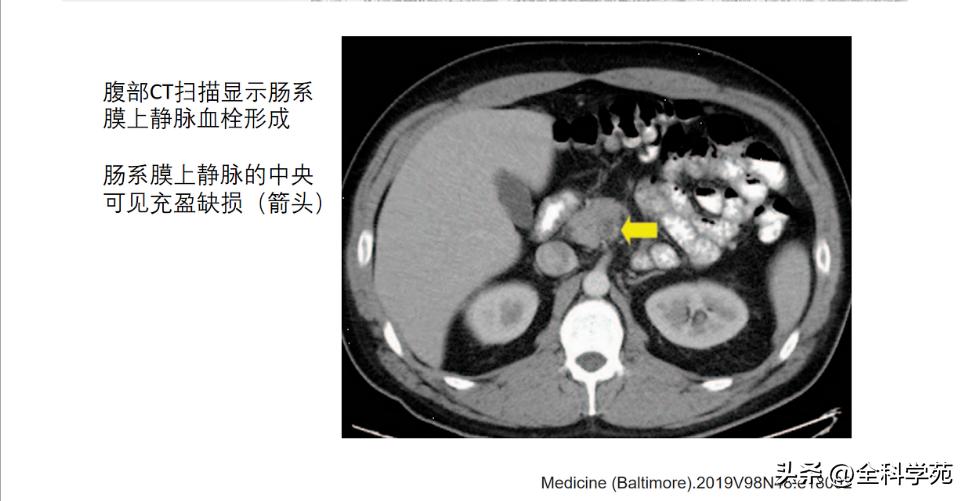

并发症( complications)

◆ 门静脉炎 (Pylephlebitis)